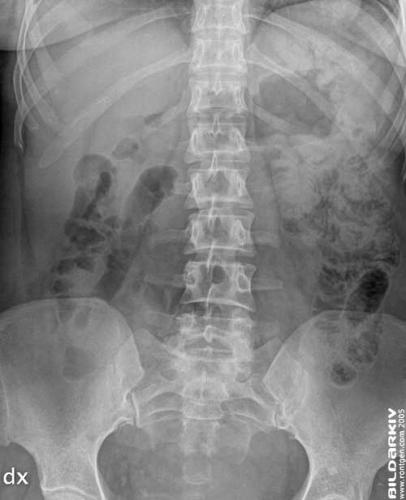

Förbild översikt frontal bild utan intravenös kontrastmedel.